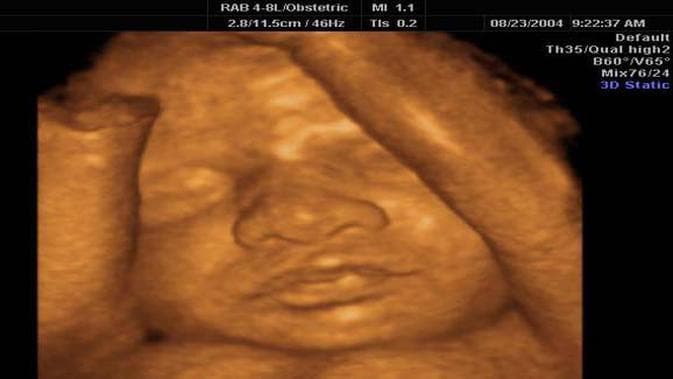

Tembang Macapat memberi gambaran tentang janin dalam kandungan sang ibu. Maskumambang memiliki arti emas yang terapung atau sering juga disebut sebagai maskentir (emas yang terhanyut). Masa kehamilan merupakan proses seluruh organ jiwa dan raga dibentuk hingga ia siap lahir ke dunia.

Proses ini berlangsung selama 280 hari atau 10 bulan atau 40 minggu yang dihitung dari hari pertama haid terakhir. Sebagian besar pemuka agama meyakini bahwa roh ditiukan pada janin ketika berusia 120 hari (dihitung sejak pembuahan terjadi).